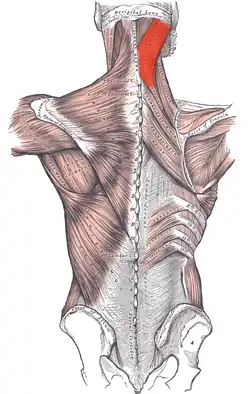

Muscles connecting the upper extremity to the vertebral column (splenius capitis et cervicis labeled at upper right). | |

The splenius capitis (/ˈspliːniəs ˈkæpɪtɪs/) (from Greek splēníon 'bandage', and Latin caput 'head'[1][2]) is a broad, straplike muscle in the back of the neck. It pulls on the base of the skull from the vertebrae in the neck and upper thorax. It is involved in movements such as shaking the head.

It arises from the lower half of the nuchal ligament, from the spinous process of the seventh cervical vertebra, and from the spinous processes of the upper three or four thoracic vertebrae.

The fibers of the muscle are directed upward and laterally and are inserted, under cover of the sternocleidomastoideus, into the mastoid process of the temporal bone, and into the rough surface on the occipital bone just below the lateral third of the superior nuchal line. The splenius capitis is deep to sternocleidomastoideus at the mastoid process, and to the trapezius for its lower portion. It is one of the muscles that forms the floor of the posterior triangle of the neck.